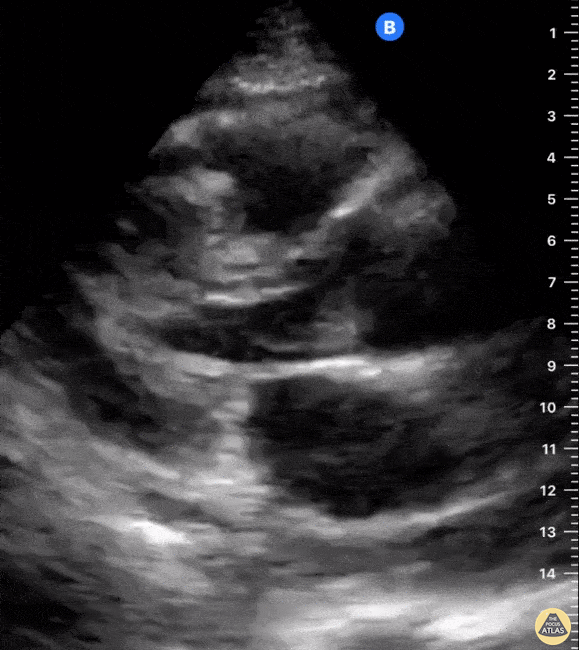

A 62-year-old female with a history of metastatic breast cancer presented with acute dyspnea and was found to have pericardial effusion with temponade physiology. Seen here in parasternal long and subsequent short axis views, POCUS demonstrates diastolic RV collapse, systolic RA collapse, and ventricular interdependence. Notice the presence of hypoechoic pericardial effusion both anteriorly and posteriorly consistent with a circumferential effusion; also note the hyperdynamic LV. Shahad Al Chalaby, MD. PGY3. Highland Hospital. Alameda Health System Internal Medicine Residency Program @shahad_Chalaby